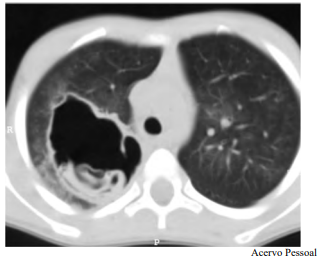

Determinado paciente de 49 anos de idade, morador em zona rural, iniciou com quadro de tosse importante, com piora progressiva, de início há dois meses, associada a alguns episódios de vômica. Refere febrículas na última semana. O paciente é tabagista leve, trabalha com criação de ovelhas e mora em casa com cachorros e gatos. Nega viagens internacionais recentes. Não foi encontrada nenhuma alteração no exame físico. Verificaram-se FC = 80 bpm, FR = 20 irpm e SatO2 = 99% em ar ambiente. A tomografia de tórax apresenta uma lesão cística de paredes espessas e conteúdo heterogêneo em seu interior, conforme representado na imagem a seguir.

Tendo em vista esse caso clínico e os conhecimentos médicos correlatos, julgue o item a seguir.

O tamanho atingido pelo cisto não tem relação com os sítios acometidos.